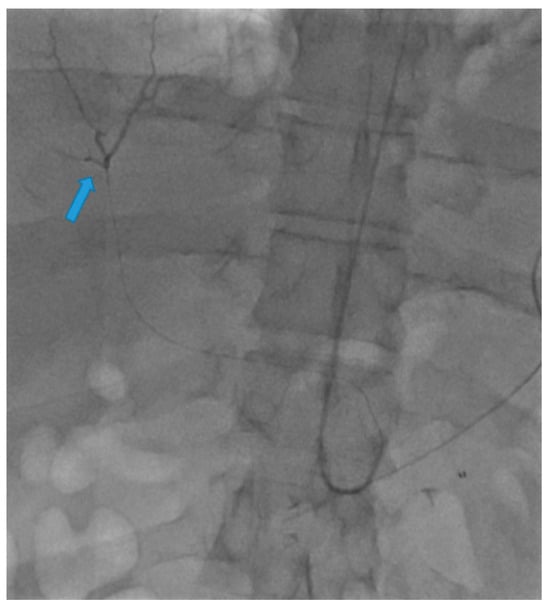

Use of Transradial Access to Install Two Sequential Stents for Pseudoaneurysms along the Celiac Artery and Common Hepatic Artery Axes